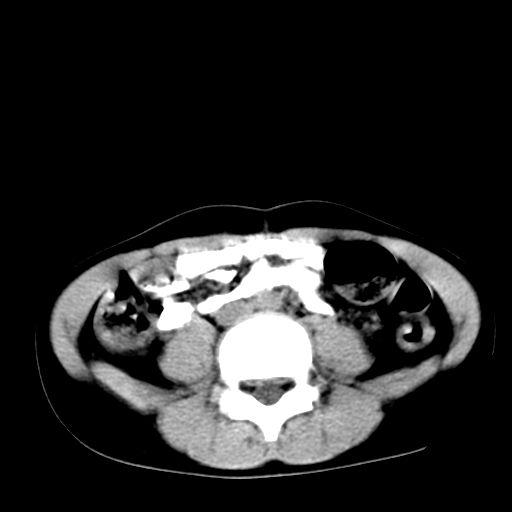

腹部好象未见异常。

腹部ct平扫未见明确异常

腹部ct平扫不能提示哪里有病变。